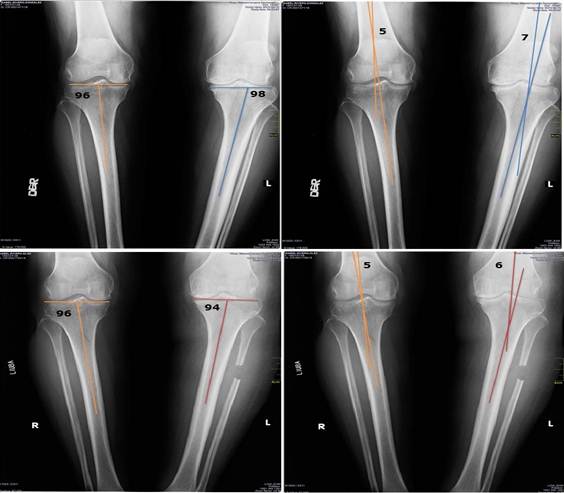

El examen radiográfico simple de ambas rodillas mostró la desviación en varo evidenciado en la medición de los ángulos tibial y femorotibial, esta deformidad fue más acentuada en la rodilla izquierda (Figura 2).

Las vistas radiográficas deben ser tomadas en la posición de pie con la rodilla flexionada unos 45 grados, lo que permite visualizar la superficie articular en toda su extensión y medir diferentes ángulos como el tibial, femoral y femorotibial, así como la distancia del espacio articular, tanto medial como lateral; estas mediciones sirven de parámetros evaluativos antes y después de realizada la técnica quirúrgica. 14,15